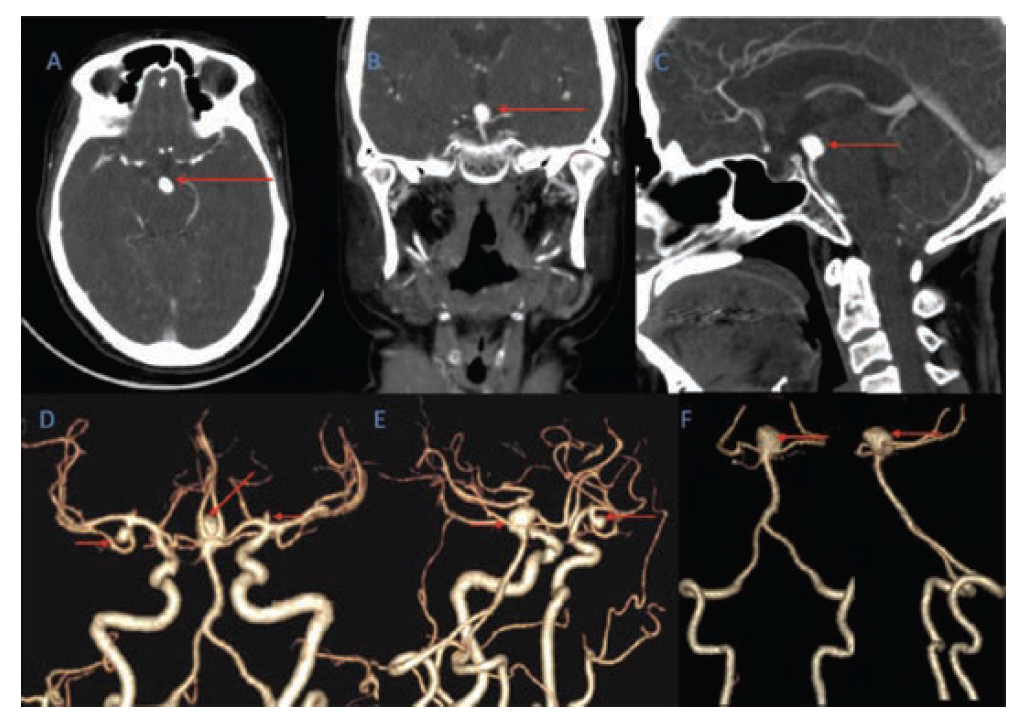

A 46-year-old woman presented with sudden onset headache associated with 2 to 3 episodes of vomiting and giddiness. On examination, her Glasgow Coma Scale (GCS) was 15/15 and power in all four limbs was 5/5. A non-contrast CT brain scan (Figure 1) revealed a diffuse SAH more predominant in the basal cisterns on the left side with intraventricular extension into the 4th ventricle (Fisher grade 4). There was no hydrocephalus. A CT angiogram (Figure 2) and diagnostic cerebral angiogram (Figure 3) demonstrated 3 intracerebral aneurysms in the following locations: inferior division of the right middle cerebral artery (MCA), 4.3 x 5 x 3.6 mm (AP x ML x CC); A1 segment of the left anterior cerebral artery (ACA), 2.1 x 2.2 x 1.4 mm; and basilar top, 11 x 8.1 x 8.3 mm with a neck measuring 6.8 mm. Based on the distribution of the SAH and morphology of the aneurysms, the basilar top aneurysm was assumed to be the cause of the SAH. Standard medical management included nimodipine, antiepileptics, antihypertensives, and analgesics.

Endovascular treatment of the aneurysm was planned. The procedure was done under general anesthesia using an Artis zee biplane (Siemens) digital subtraction angiography system (Figure 4 and Figure 5). The right femoral artery was accessed. The right vertebral artery angiogram showed no change in the aneurysmal morphology when compared with the previous diagnostic angiogram performed 6 days earlier. Intra-arterial nimodipine (2 mg) was injected slowly over 15 minutes. A 6 Fr Neuron MAX (0.088" x 80 cm) (Penumbra) long sheath was placed in the right subclavian artery at the vertebral artery origin. Using a 0.035" Glidewire (Terumo Interventional Systems) and a 6 Fr Navien (0.072" x 115 cm) (Medtronic) intermediate guiding catheter combination, the right vertebral artery was cannulated and the tip of the Navien was placed at the junction of the V2 and V3 segment over the wire. Using a Synchro (0.014" soft x 200 cm) (Stryker) microwire with an Echelon-10 (0.017") (Medtronic) microcatheter combination, the aneurysm was catheterized with a microcatheter within the sac; this was later used for coiling. With a Synchro 0.014" wire and NeuroSlider 0.021" (Acandis) microcatheter combination, the aneurysm was cannulated with a microcatheter tip just above the neck; this was used for the endosaccular device. A Neqstent endosaccular device (Cerus Endovascular) 11 mm was selected according to the chart provided by Cerus Endovascular. It was advanced through the NeuroSlider and deployed just above the aneurysm neck while the Echelon-10 microcatheter was jailed within the aneurysm sac.

Subsequently, coiling of the aneurysm sac was performed using multiple 3D framing and 2D filling coils (Axium Prime, Medtronic) 3D ev3 coils (8 mm x 20 cm and 6 mm x 20 cm; 2 in number) and Axium Helix (Medtronic) 2D coils (4 mm x 10 cm, 3 mm x 10 cm, 3 mm x 8 cm, and 2.5 mm x 8 cm). Check angiograms were performed to look for the position of the Neqstent. Slight pull-and-push manipulation of the Neqstent was done after partial coiling so it formed a better shape snugly across the wide neck, providing better scaffolding for coiling. Once coiling was completed, the microcatheter was withdrawn from the aneurysmal sac. The Neqstent was detached using its electrolytic detachment system, after confirming its proper position. Post-coiling cerebral angiogram (Figure 5) showed complete occlusion of the basilar top aneurysm with good flow across the bilateral posterior cerebral arteries, the basilar artery, and its major branches. A simple line diagram (Figure 6) depicts the placement of a coiling microcatheter adjacent to the deployment of the Neqstent. Heparinization was maintained with 5000 IU of initial bolus and additional 1000 IU every hour.